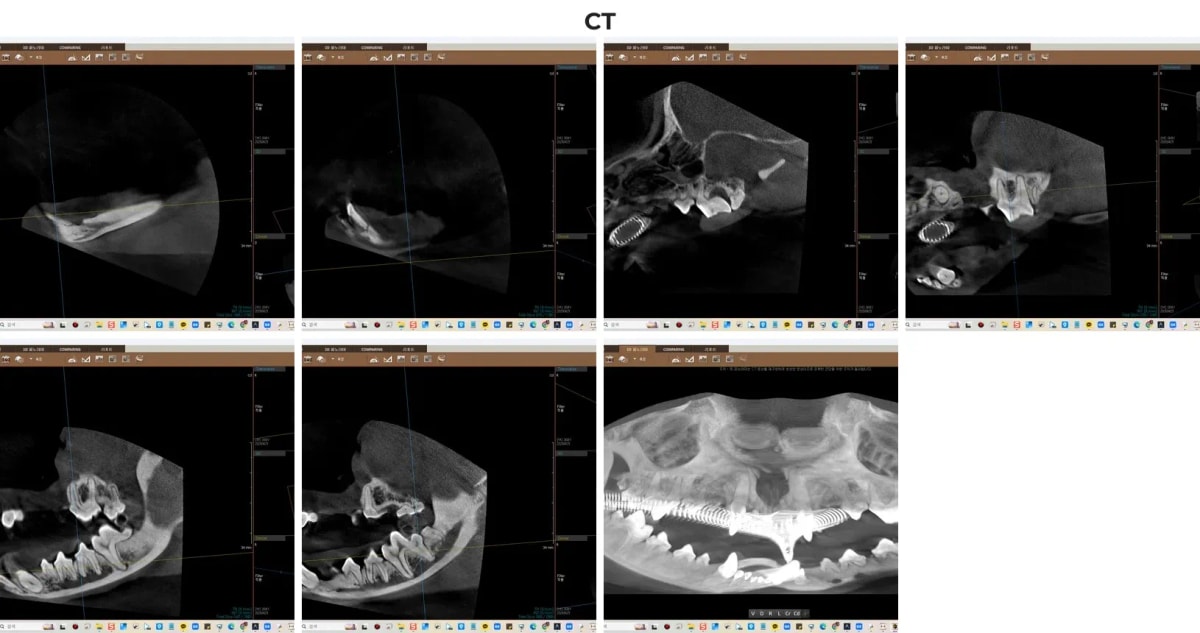

2. 치과 전용 CT 진단의 중요성

ℹ️ 치과 CT의 중요성

눈이나 일반 엑스레이만으로는 치아 뿌리가 주변 잇몸뼈(치조골)나 신경에 얼마나 가깝게 맞닿아 있는지 정확히 파악하기 어렵습니다. 특히 레오처럼 영구치와 유치가 뒤엉켜 있거나 치아 파절이 동반된 경우, 광주·전남 유일의 동물 전용 치과 CT를 통한 3D 입체 분석은 턱뼈 손상 없이 안전한 수술 계획을 세우는 데 필수적입니다.

광주 강아지 치과 CT 정밀 진단

3. 수술 전 구강 엑스레이 평가

CT 촬영 후, 수술 시야에 맞춘 국소적인 구강 방사선(X-ray) 촬영을 병행했습니다. 영상 분석 결과, 상악과 하악에 남아있는 유치 송곳니들(504, 604, 704, 804번)의 뿌리 상태와 영구치의 위치 관계를 명확히 확인했습니다. 하악 유치는 이미 부러진 상태로 치아 흡수성 병변이 진행 중이었고, 좌측 상악 어금니(208번)에는 파절 소견이 보였습니다. 정밀한 영상 진단은 불필요한 잇몸 절개를 막고, 꼭 필요한 보존 치료만 선별하는 기준이 됩니다.